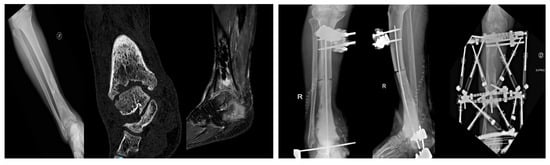

Management and Treatment Strategies for Distal Tibia and Ankle Infections: Our Clinical Experience

by Antonio Mascio, Chiara Comisi, Carmen Barlotti, Tommaso Greco, Federico Moretti, Virginia Cinelli, Andrea De Fazio, Giovan Giuseppe Mazzella, Giulio Maccauro and Carlo Perisano

Background: The management of infections involving the distal tibia and ankle is a significant challenge in orthopedic surgery due to complex anatomy and the high risk of complications. The study aims to present our clinical experience in managing these infections and focusing on [...] Read more.

Background: The management of infections involving the distal tibia and ankle is a significant challenge in orthopedic surgery due to complex anatomy and the high risk of complications. The study aims to present our clinical experience in managing these infections and focusing on surgical strategies, infection control, and functional outcomes over a minimum 24-month follow-up period. Methods: This is an observational, retrospective case series of 17 patients treated for osteoarticular infections of the distal tibia and/or ankle between January 2020 and May 2023, in a second-level referral trauma center. A staged surgical approach was employed, including radical debridement, temporary stabilization with external fixation, and, in most cases, implantation of a cement spacer loaded with antibiotics. Functional outcomes were assessed using scores such as EQ-5D-5L. Results: The cohort was predominantly male (76.5%), with a high prevalence of elevated BMI and comorbidities. Infection onset was most frequently associated with open fractures (64.7%). Staphylococcus aureus was the most common isolated pathogen (41.2%), and infections caused by Gram-negative or multidrug-resistant bacteria were associated with more reoperations. Overall, complications occurred in 10 patients (58.8%), requiring reintervention in 9 patients (52.9%). Limb salvage was achieved in 16 of 17 patients (94.1%). Conclusions: Our study highlights the critical role of a tailored, multidisciplinary approach in managing these complex infections. Meticulous surgical planning and proactive management of complications are essential for optimizing patient outcomes. Full article